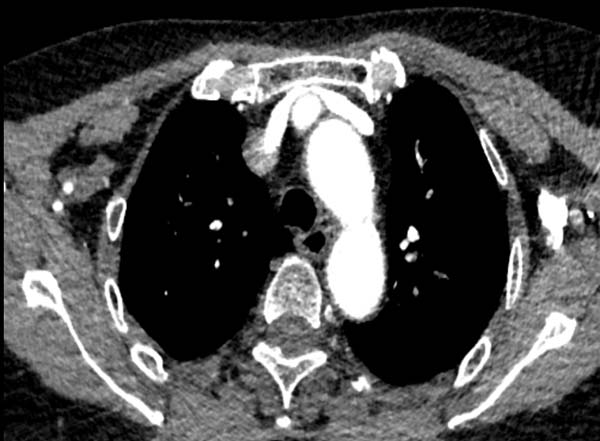

1) 由于受主动脉压迫导致对比剂冲入浅表静脉网中,受阻严重导致团注效果不佳。

头臂干压迫左头臂静脉

左侧锁骨下静脉受主动脉弓挤压,

导致对比剂冲入浅表静脉网中

左侧锁骨下静脉受主动脉弓挤压 血管充盈不佳